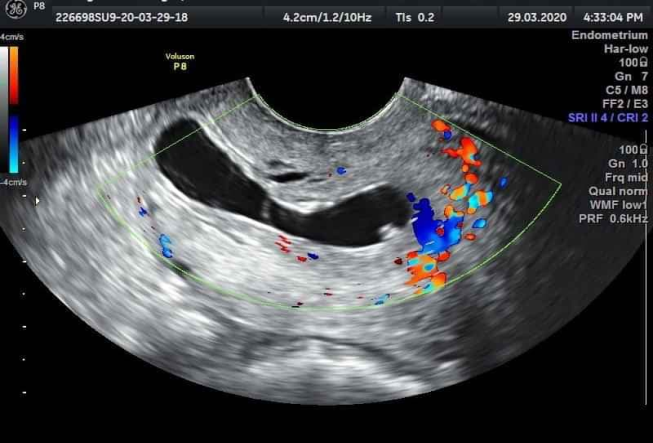

Bệnh nhân L.T.N.H 42 tuổi, PARA (2092) 2 lần sinh thường, 9 lần sẩy thai có nhiều lần can thiệp buồng tử cung, trể kinh, thử thai dương tính đi khám tại phòng khám tư nhân với chẩn đoán thai làm tổ ống cổ tử cung, bệnh nhân được nhập viện cùng ngày, lâm sàng trể kinh 2 tuần, không đau bụng, không ra máu âm đạo, đặt mỏ vịt thấy cổ tử cung lớn, mạch máu tăng sinh nhiều, nổi rõ mạch lên tại vùng cổ tử cung, cổ tử cung hở lỗ ngoài, siêu âm thai 6 tuần tại vị trí cổ tử cung, tim thai dương tính, phổ Doppler thấy tăng sinh mạch mạnh tại vùng cổ tử cung và có tính hiệu Doppler màu tại bánh nhau.Bệnh nhân được làm xét nghiệm công thức máu, chức năng gan, thận và chức năng đông máu trong giới hạn bình thường. Bệnh nhân theo dõi tại viện sau 3 ngày (vào viện chiều thứ 6) và hội chẩn khoa tại phòng siêu âm: chẩn đoán thai 6 tuần 3 ngày làm tổ tại cổ tử cung, tim thai dương tính. Xét nghiệm beta hCG 78352 mIU/ml, được chỉ định điều trị tiêm MXT tại chổ và hóa trị liệu toàn thân bằng MTX: Tiến hành hút hết ối, tiêm MTX tại khối thai 25 mg, tại bánh nhau 25 mg, sau 2 tiếng kiểm tra tim thai âm tính tiêm bắp MTX25 mg (tổng liều 75mg). Sau 3 ngày bệnh nhân xuất hiện đau bụng vùng dưới, tiến hành nạo gắp khối thai chủ động bằng kẹp đầu vợt, máu tại cổ tử cung ra nhiều, dùng sonde foley số 16 bơm từ từ lên 50 ml nước thì cầm được máu, lưu sonde, theo dõisau 20 phút bóng tuột, tiến hành đặt lại bóng với 50 ml nước muối, sau đó chèn gạc kín âm đạo, sau 24 giờ rút sonde, không còn ra máu. Kết quả xét nghiệm lại β-hCG 4626 mIU/ml. Bệnh nhân được cho ra viện sau đó 2 ngày. Sau một tuần xét nghiệm β-hCG 343.18 mIU/ml, sau 5 tuần β-hCG 2.42 mIU/ml. siêu âm tử cung phần phụ chưa phát hiện bất thường.

Hình 1. Hình ảnh siêu âm đầu dò âm đạo túi thai làm tổ tại cổ tử cung; cổ tử cung phình to; dòng máu xung quanh nguyên bào nuôi thấy trên phổ Doppler